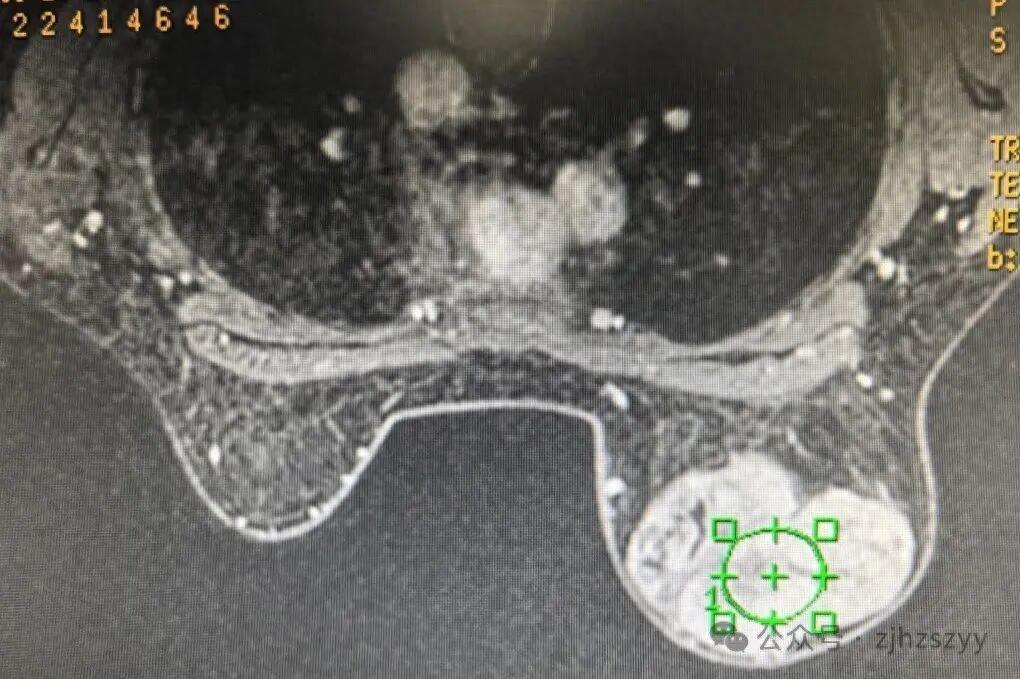

24岁的杭州女孩小刘, 为了拼事业经常熬夜,一年后洗澡时突然发现右乳里长了个拳头大的硬疙瘩,她还以为是正常的经期胀痛,没当回事。可谁知道,这疙瘩长得飞快,一年后直接长到了12厘米,几乎把整个右乳都撑得满满的! 去医院检查后,医生告诉她这是“叶状肿瘤”——虽然大多是良性的,但长得特别快,要是再拖下去可能就危险了。手术的时候,医生特意选了隐蔽的切口,还放了假体,这样乳房的形状能保持好看。手术后小刘才后怕:“早知道这样,当初就该早点来医院的...” 医生特别提醒:发现乳腺上有肿块,千万别拖着不管!叶状肿瘤就跟野草似的,要是不早点彻底处理掉,很可能会反复长。特别是年轻的女孩子,工作再忙,每个月洗澡的时候,花一分钟自己检查一下,就能避免大问题找上门。 有网友就说:现在的年轻人啊,真是太拼了!体检报告都不敢看,小毛病拖成了大问题,最后还得躺手术台。你身边有没有这样“硬扛着不吭声”的职场人呢?你平时会给自己做乳房自检吗?评论区聊聊你的小习惯吧~